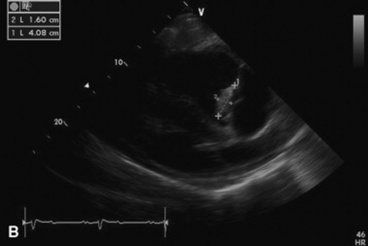

Echocardiograms should also be performed from the left cardiac window when the entire heart cannot be successfully imaged from the right side; atrial fibrillation is present; abnormalities of the mitral valve, aortic valve, pulmonic valve, aorta, pulmonary artery, left atrium, left ventricle, or outflow portion of the interventricular septum are detected; or murmurs originating from the mitral, aortic, or pulmonic valves are detected or a pericardiocentesis is planned. The maximal diameter of the left atrium should be obtained from the left cardiac window at the level of the left coronary artery, parallel to the mitral valve (Fig. 30-3). The diameters of the aorta and pulmonary artery should be measured from similar locations in the vessel on the two-dimensional echocardiogram and compared. Echocardiography should be considered a useful diagnostic test to evaluate patients with the following complaints, physical examination findings, or tentative diagnoses:

image

Fig. 30-3 Two-dimensional echocardiographic image of the left atrial diameter obtained from the left parasternal long axis window in a horse with mild left atrial enlargement secondary to cardiomyopathy and mitral regurgitation.